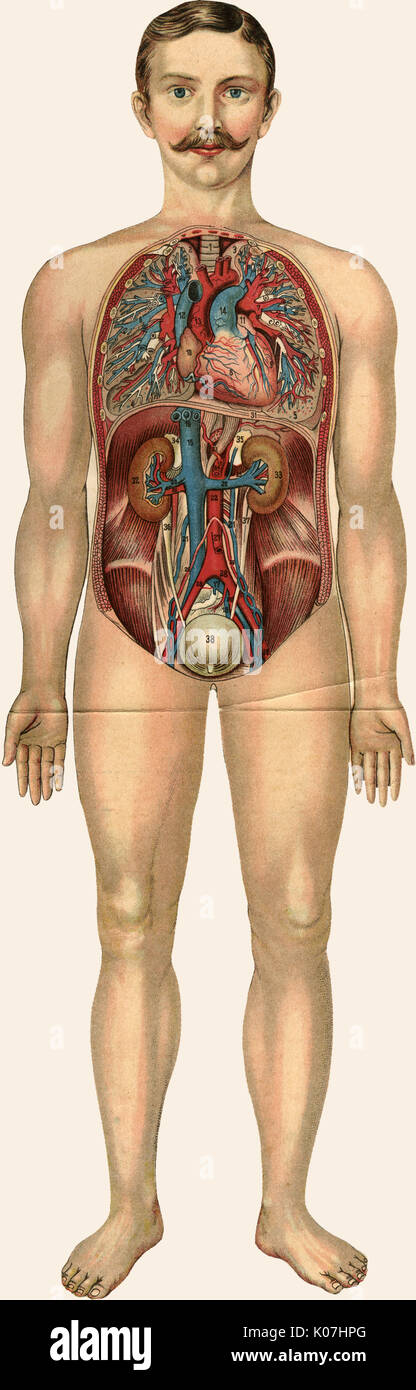

RFPAYTH0–Innere Organe, männlichen Körper - schematische Darstellung der menschlichen Anatomie Illustration - auf weißem Hintergrund.